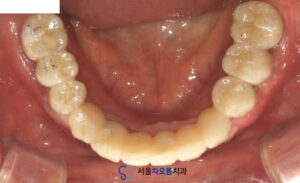

25.03.21 / 25.07.06

치료 전후 사진입니다.

환자분께서는 치료 이후

식사를 편하게 하실 수 있고

보철도 심미적으로 완성되어

매우 만족해주셨습니다.